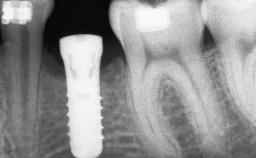

A 20-year-old woman was referred for implant therapy in 2004. Her medical history revealed no significant findings, and neither did she smoke nor take any medications. An extraoral examination revealed no abnormalities of the skin, hair or nails. The intraoral examination revealed only 11 permanent teeth clinically. These were normal in shape, size, and color. In addition, eight retained deciduous teeth (53, 62, 63, 71, 72, 73, 81, 82) were present. No abnormalities were detected during the general examination. The family history revealed that the patient’s father and two sisters were on record with similar conditions. The clinical examination revealed a thick gingival biotype. No recession of the attached gingiva was noted, but the retained deciduous teeth were mobile and unsightly. As a syndrome had not been diagnosed, the case was categorized as non-syndromic oligodontia.

# of Implants 12

Type of Implants One-Piece|Reduced-Diameter

Bone Volume Deficient horizontally, requiring prior grafting